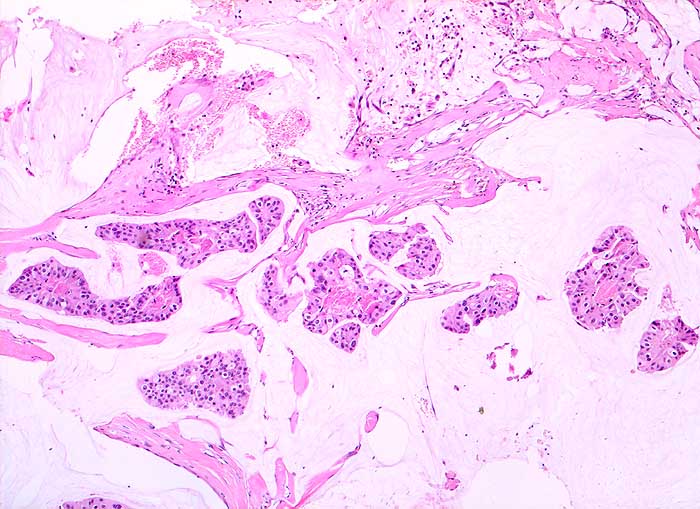

Homogene oder schlierenförmige extrazelluläre Schleimmassen mit Inseln von Tumorzellen mit geringen Kernatypien sind pathognomonisch für das muzinöse Mammakarzinom. Die Zellzahl ist meist nicht sehr hoch. Die Zellen liegen einzeln oder in kleinen kugeligen oder pseudopapillären Verbänden. Der Schleim erscheint in der Pap Färbung blau-grau bis rötlich. Siegelringkarzinome zeigen grössere intrazytoplasmatische Schleimvakuolen.

Unten werden zwei Beispiele von typischen muzinösen Karzinomen gezeigt.